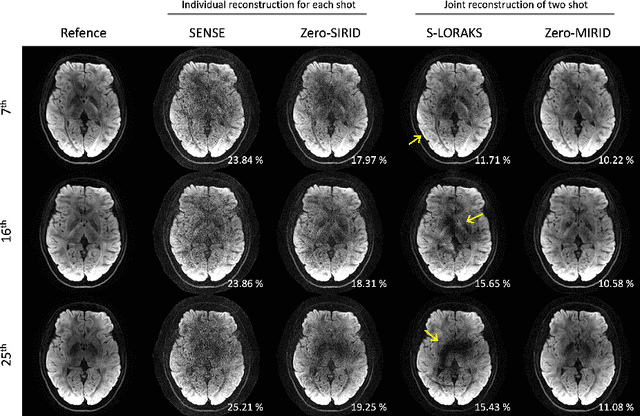

Abstract:Diffusion MRI is commonly performed using echo-planar imaging (EPI) due to its rapid acquisition time. However, the resolution of diffusion-weighted images is often limited by magnetic field inhomogeneity-related artifacts and blurring induced by T2- and T2*-relaxation effects. To address these limitations, multi-shot EPI (msEPI) combined with parallel imaging techniques is frequently employed. Nevertheless, reconstructing msEPI can be challenging due to phase variation between multiple shots. In this study, we introduce a novel msEPI reconstruction approach called zero-MIRID (zero-shot self-supervised learning of Multi-shot Image Reconstruction for Improved Diffusion MRI). This method jointly reconstructs msEPI data by incorporating deep learning-based image regularization techniques. The network incorporates CNN denoisers in both k- and image-spaces, while leveraging virtual coils to enhance image reconstruction conditioning. By employing a self-supervised learning technique and dividing sampled data into three groups, the proposed approach achieves superior results compared to the state-of-the-art parallel imaging method, as demonstrated in an in-vivo experiment.